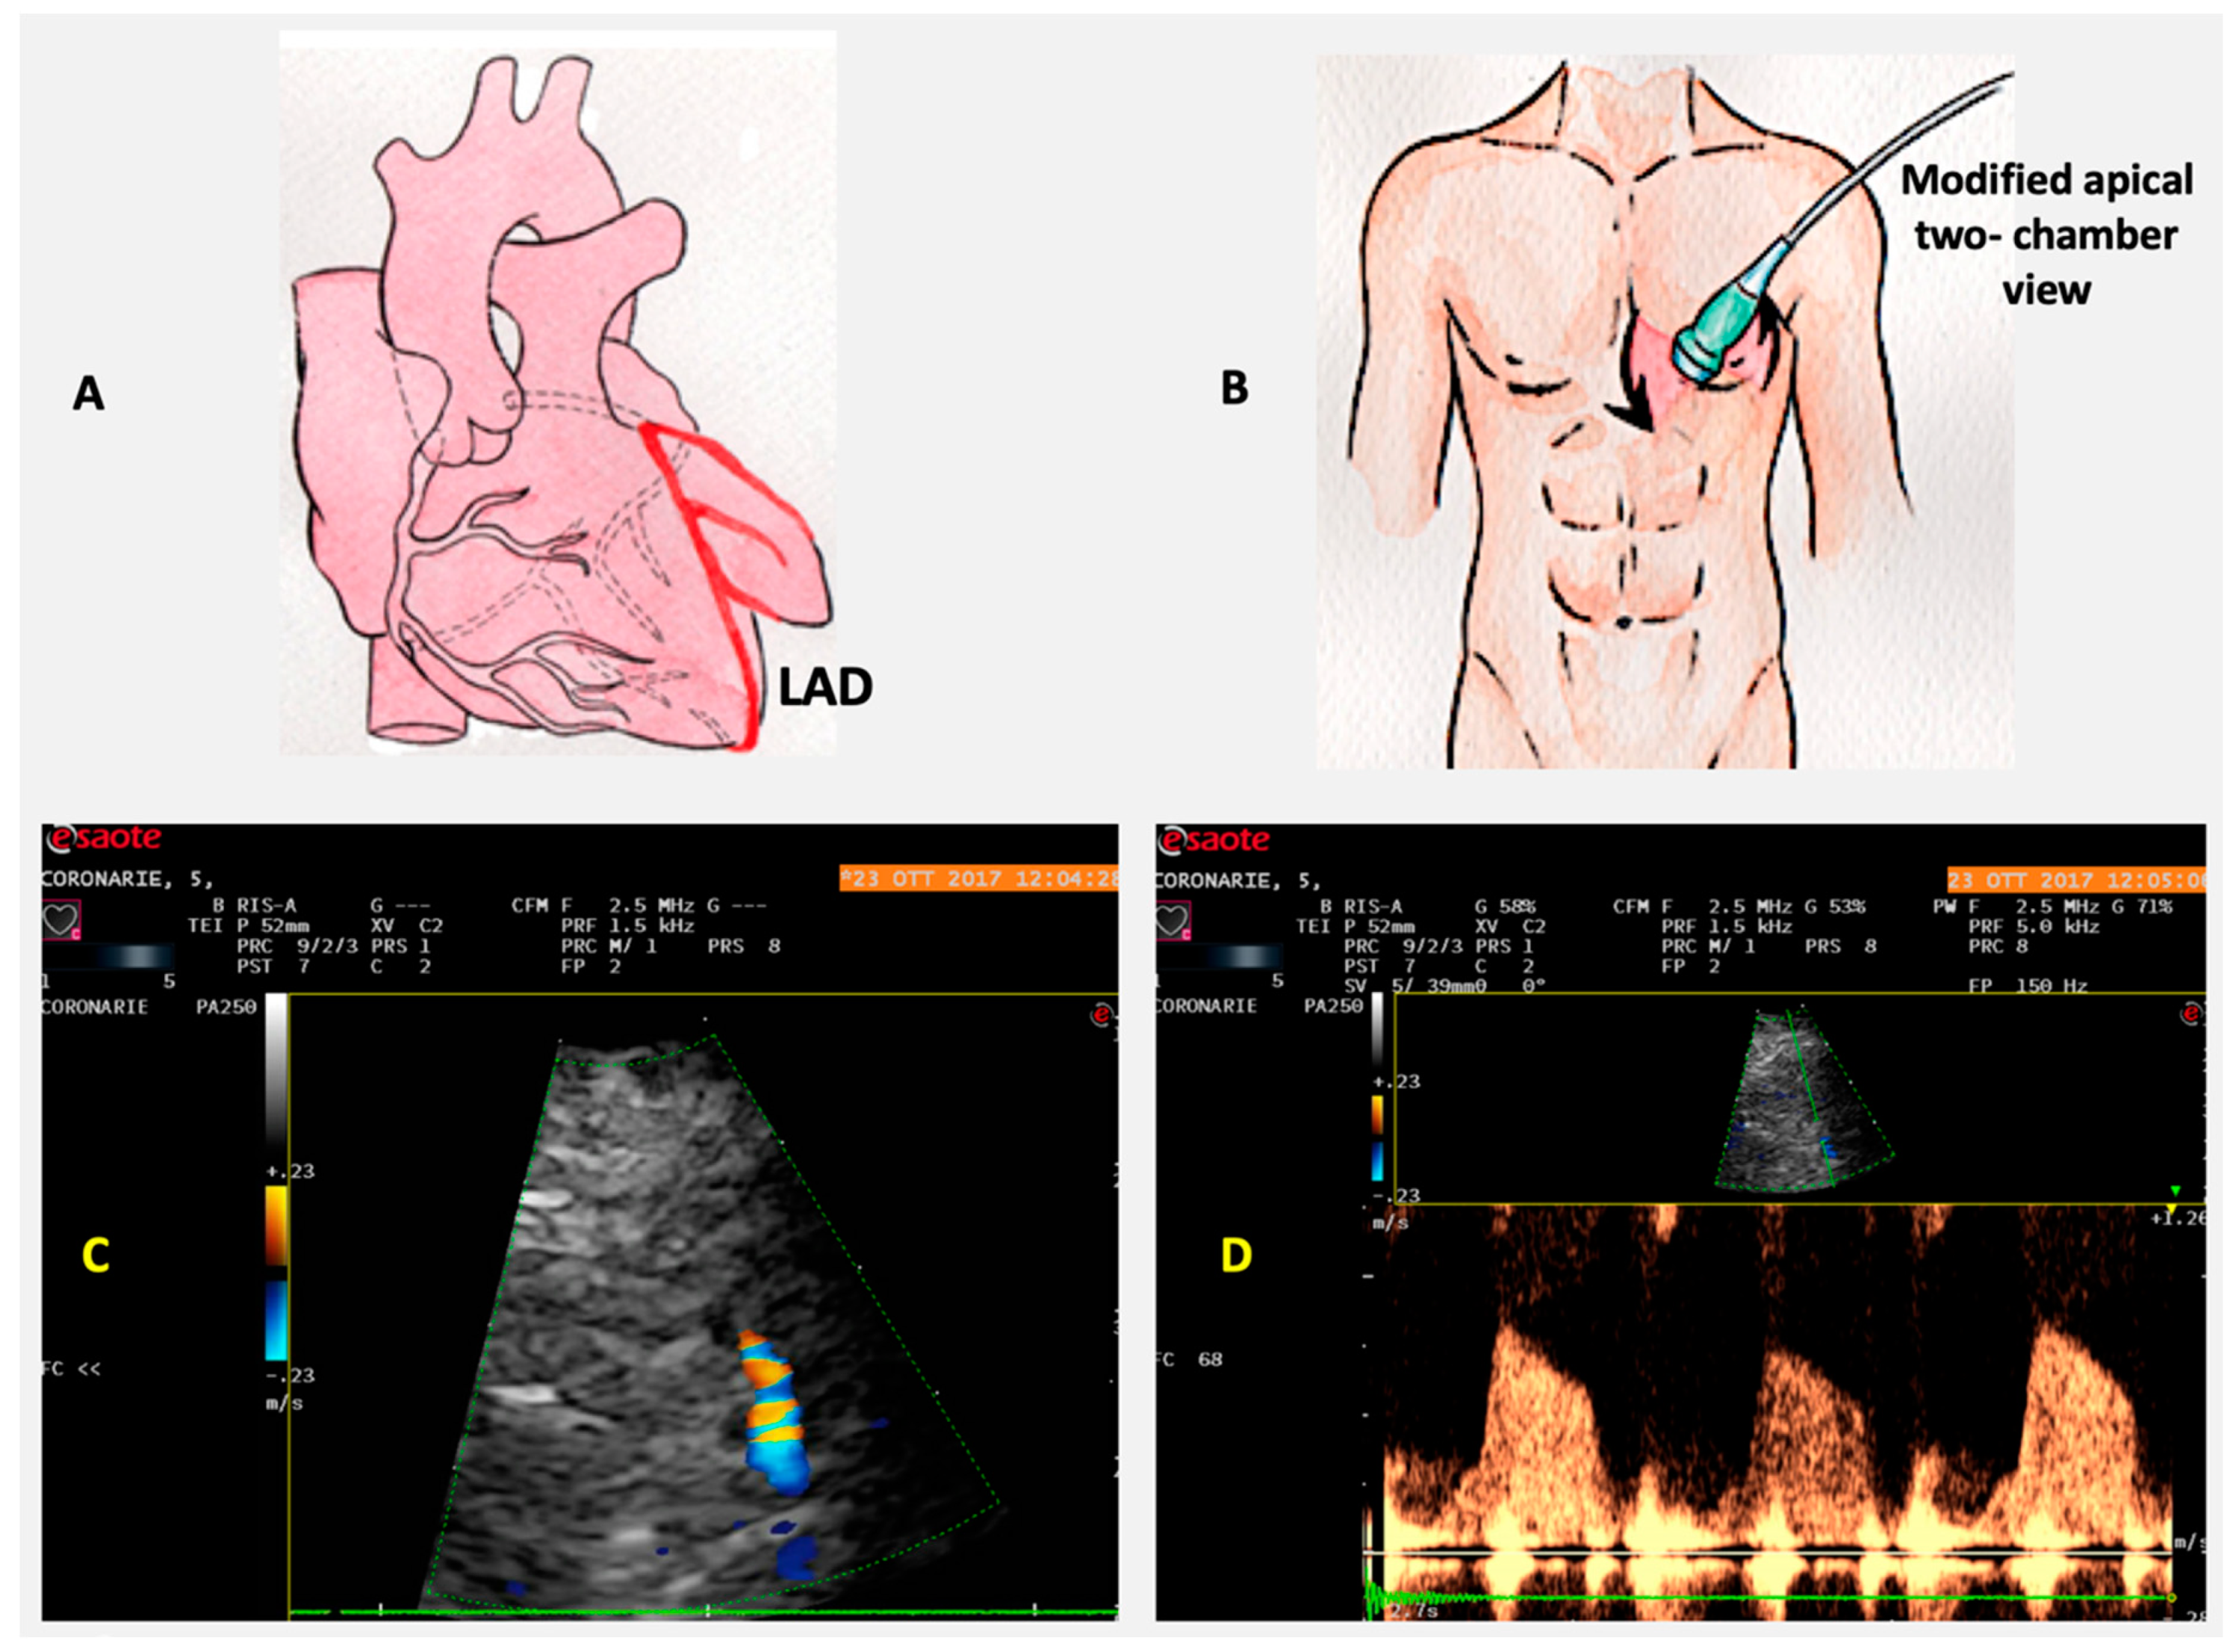

6. Coronary Flow Reserve

Role of CFR in IHD

- Gan, L.-M.; Svedlund, S.; Wittfeldt, A.; Eklund, C.; Gao, S.; Matejka, G.; Jeppsson, A.; Albertsson, P.; Omerovic, E.; Lerman, A. Incremental value of transthoracic doppler echocardiography-assessed coronary flow reserve in patients with suspected myocardial ischemia undergoing myocardial perfusion Scintigraphy. J. Am. Heart Assoc. 2017, 6, e004875. [Google Scholar] [CrossRef]

- Haraldsson, I.; Gan, L.-M.; Svedlund, S.; Wittfeldt, A.; Råmunddal, T.; Angerås, O.; Albertsson, P.; Matejka, G.; Omerovic, E. Non-invasive evaluation of coronary flow reserve with transthoracic Doppler echocardiography predicts the presence of significant stenosis in coronary arteries. Int. J. Cardiol. 2014, 176, 294–297. [Google Scholar] [CrossRef]

- Rahmani, M.; Cruz, R.P.; Granville, D.J.; McManus, B.M. Allograft Vasculopathy versus atherosclerosis. Circ. Res. 2006, 99, 801–815. [Google Scholar] [CrossRef]

- Sade, L.E.; Eroğlu, S.; Yuce, D.; Bircan, A.; Pirat, B.; Sezgin, A.; Aydınalp, A.; Muderrisoglu, H.; Bircan, A.; Aydinalp, A. Follow-up of heart transplant recipients with serial echocardiographic coronary flow reserve and Dobutamine stress echocardiography to detect cardiac allograft Vasculopathy. J. Am. Soc. Echocardiogr. 2014, 27, 531–539. [Google Scholar] [CrossRef]